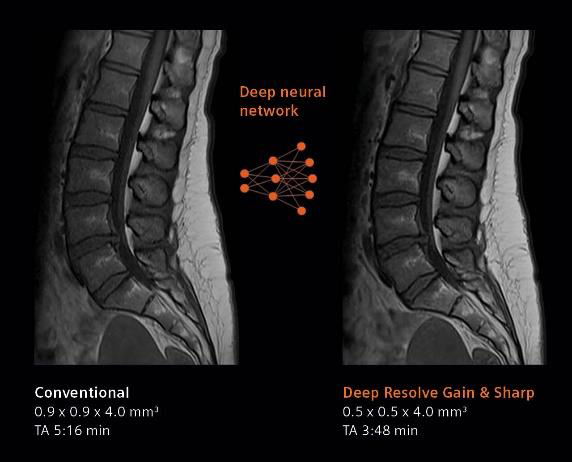

デジタル化により高画質と撮像時間の短縮を実現するべく、画像再構成にAI技術を用いて開発されたのがDeep Resolve(ディープ・レゾルブ)だ。

Deep Resolveは、ディープラーニング(深層学習)とターゲットデノイジング(ノイズの標的除去)により画像のノイズ除去や撮像した画像を高分解能化することで、高品質な画像の取得と撮影時間の短縮*1を可能にする。検査精度やワークフローの向上のほか、被検者の快適性や質の高い医療へのアクセス向上が期待される。